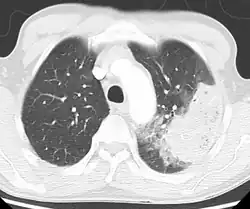

Cavitating pneumonia due to MRSA as seen on a CT scan

Bacteria are the most common cause of community-acquired pneumonia (CAP), with Streptococcus pneumoniae isolated in nearly 50% of cases.[42][43] Other commonly isolated bacteria include Haemophilus influenzae in 20%, Chlamydophila pneumoniae in 13%, and Mycoplasma pneumoniae in 3% of cases;[42] Staphylococcus aureus; Moraxella catarrhalis; and Legionella pneumophila.[22] A number of drug-resistant versions of the above infections are becoming more common, including drug-resistant Streptococcus pneumoniae (DRSP) and methicillin-resistant Staphylococcus aureus (MRSA).[24]